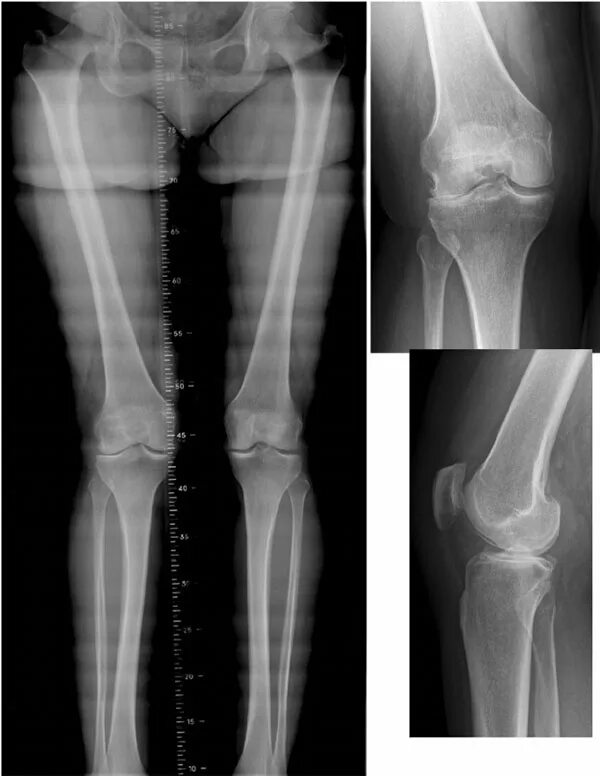

Вальгусная деформация коленных суставов у ребенка